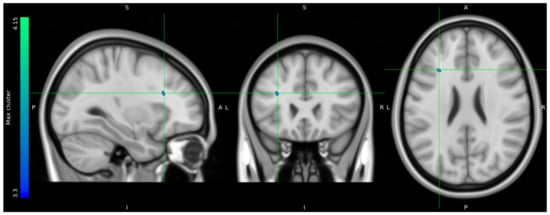

Due to data loss on the scanner, only 8 HCs and 10 stress patients were included in the brain imaging analysis. The one-tailed t-tests performed to evaluate voxels for which there was a directional-specific group difference (i.e., HC > stress or HC < stress) only showed effects in the HC > stress group. The one-tailed t-tests evaluating voxels for which there was a directional-specific group difference driven by a hypometabolic effect in stress patients compared to HCs identified three clusters with MNI coordinates [−30 24 24], left frontal lobe sub-gyral adjacent to middle frontal gyrus, [28 8 44] right frontal lobe middle frontal gyrus, and [12 −16 68] right frontal lobe precentral gyrus. Noticeably, the identified cluster appeared primarily to be located in the WM regions (Figure 5).

Figure 5.

FDG uptake illustrating a difference in glucose consumption between stress patients and healthy controls. Here, projected on MNI standard space template MNI152 0.5 with intensity threshold defined in color bar on the left. A: anterior, P: posterior, S: superior, I: inferior, L: left, R: right.

The results of the adapted version of the SCAN interview showed a clinical direction of stress patients experiencing physiological dysfunction as well as mental challenges in higher brain functions related to executive functions and emotion and mood regulation. Our FDG-PET imaging group analysis identified three clusters of voxel-wise differences in cerebral glucose metabolism between stress patients and HCs, where the stress patients had hypometabolic effects in areas primarily located in the white matter of the prefrontal cortex. The extracted suprathreshold cluster mean FDG uptake values for each participant expresses a consistent difference in the distribution between stress patients and HCs.